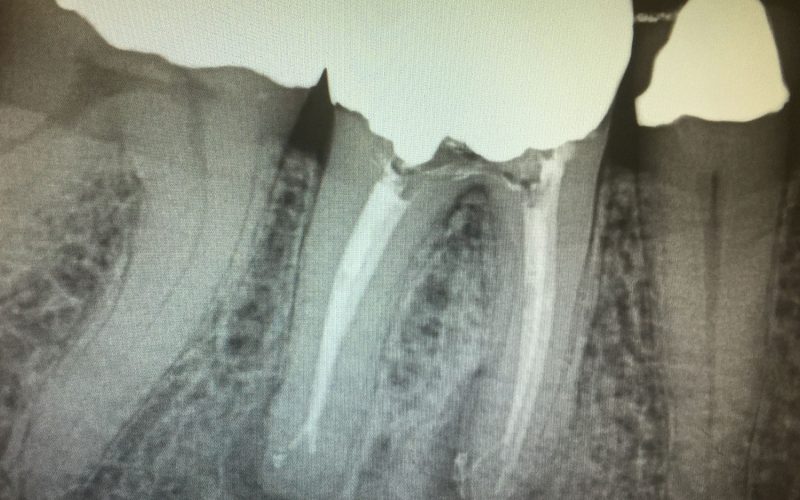

Once retreatment has been selected as a treatment alternative, the doctors will numb you up and regain access to the inside of your tooth. The original restorative material will be removed to enable access to the root canal. The doctors will shaped and clean the canals and microscopically examine the inside of the tooth for the presence of additional canals, contaminated tissues, or the presence of fractures. Once shaped and cleaned, the doctors will fill the canals to prevent microbes from colonizing the area and place either a temporary or a final filling.